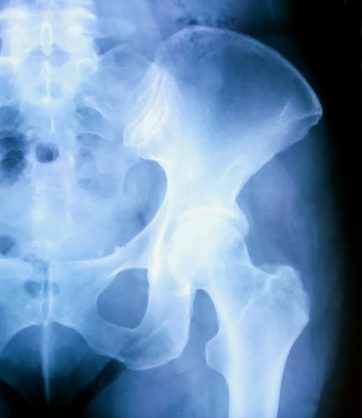

骨盤を調整することで身体全体のバランスと軸が通り外見的な変化(姿勢やプロポーション)だけでなく、呼吸・循環・自律神経・女性ホルモンの流れにもアプローチが可能です。